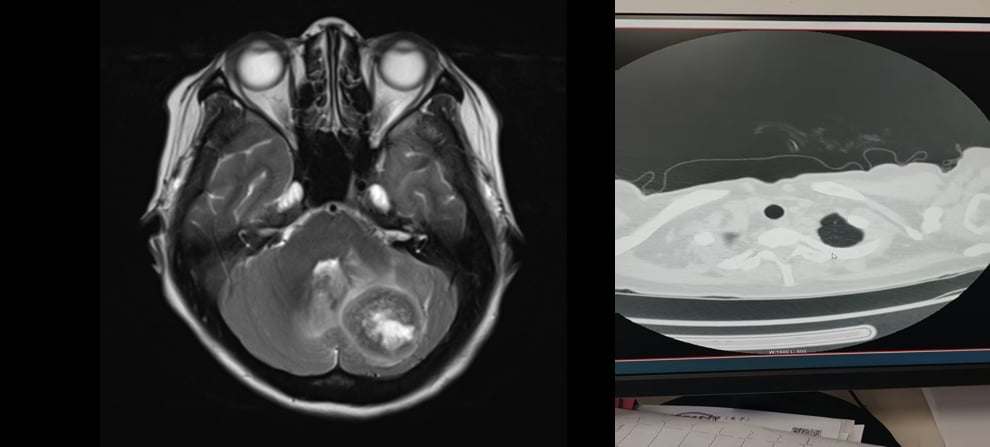

我们来看一个真实的案例:一位45岁的女性患者,因持续性头痛就诊。经过详细检查,确诊为右侧乳腺恶性肿瘤(c4N3M1 IV期),伴有左侧小脑转移、腋窝淋巴结转移、肺转移、纵膈淋巴结转移。病理报告显示为浸润性乳腺癌,非特殊型,Ⅱ级,免疫组化结果为Her-2(2+),FISH检测结果提示Her-2阳性,ER(-)、PR(-),Ki-67(+,局部约30%)。这意味着患者是HER2阳性且激素受体阴性的晚期乳腺癌,预后通常较差。初诊时,患者的PS评分(体能状态评分)为3-4分,表明其身体状况非常虚弱,生活自理能力受限。PET-CT影像学检查进一步证实了右侧乳腺占位累及皮肤及前胸壁软组织,双肺多发肿块及结节灶,左侧小脑半球占位,以及全身多发淋巴结肿大,FDG代谢均异常增高,提示肿瘤活性高。

经过3个周期的治疗后,医生对患者的疗效进行了评估。结果令人振奋:颅内病灶从部分缓解(PR)进一步达到了完全缓解(CR)!这意味着患者大脑中的肿瘤病灶已经完全消失,这对于晚期乳腺癌脑转移患者来说,无疑是一个巨大的胜利,也是德曲妥珠单抗强大疗效的有力证明。患者的乳腺原发灶也明显缓解,全身肿瘤负荷显著降低。这个案例充分展示了德曲妥珠单抗在HER2阳性乳腺癌伴脑转移治疗中的巨大潜力,为无数患者带来了生的希望。